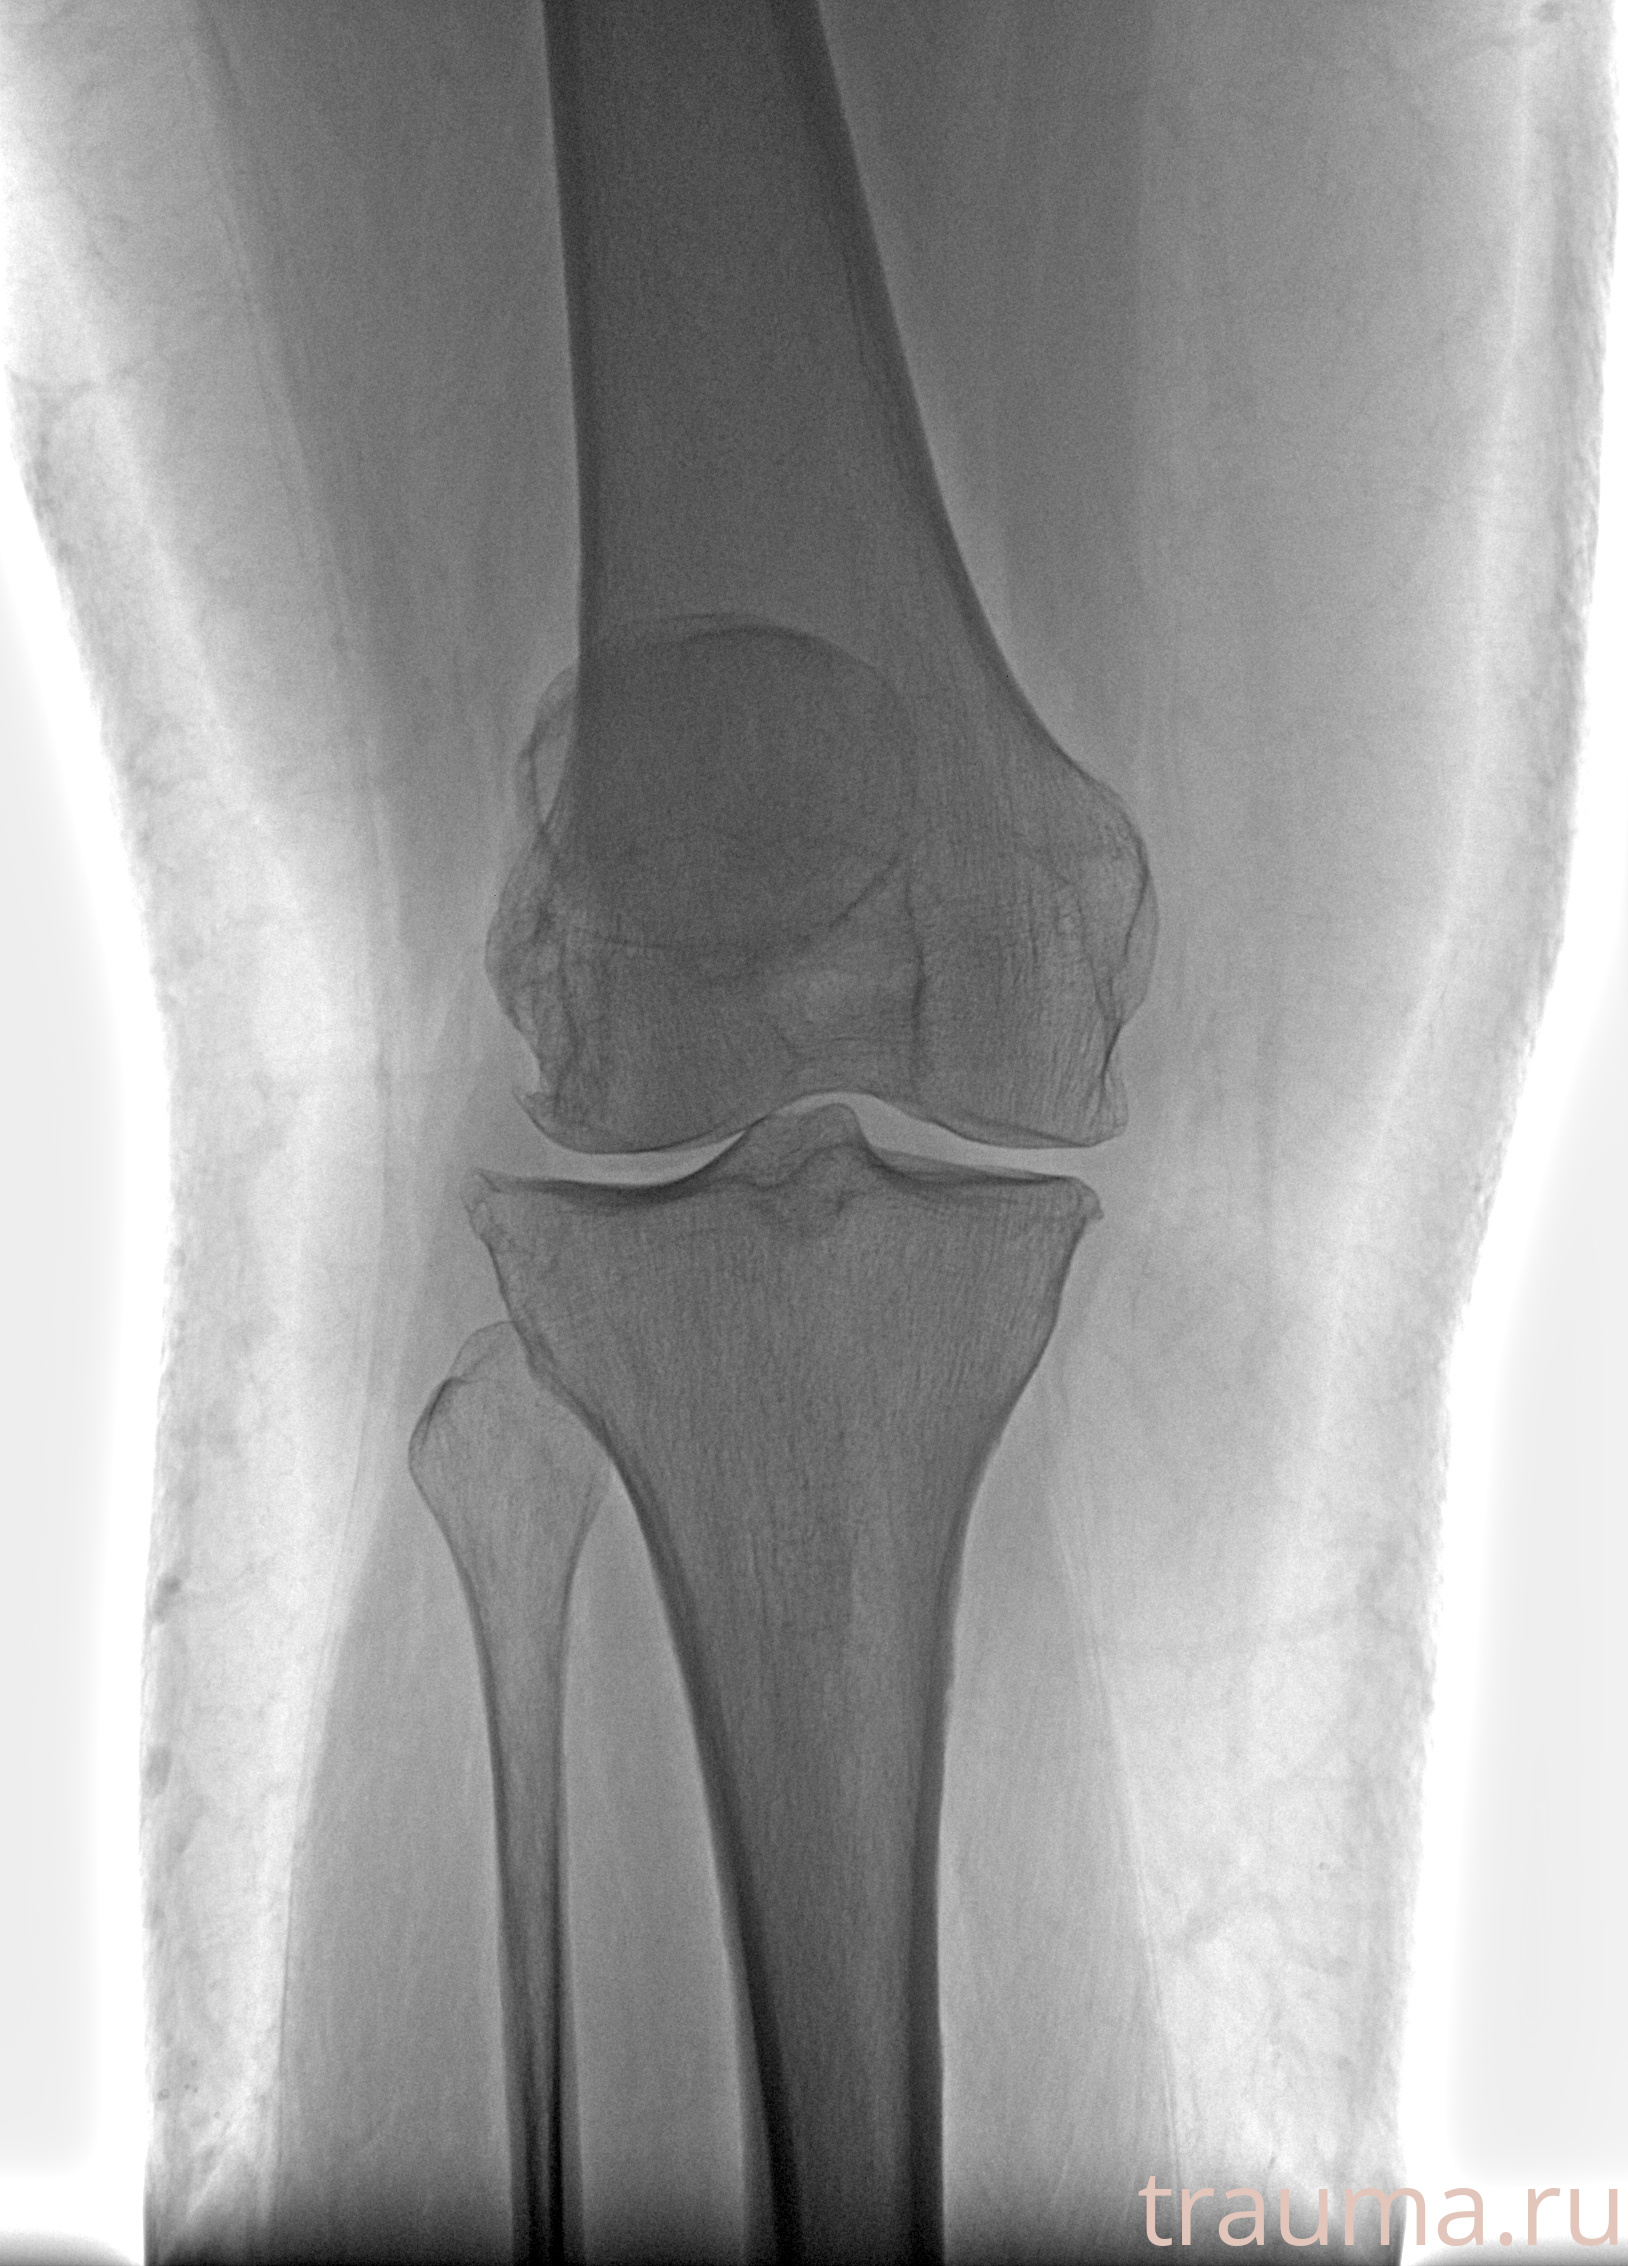

Рентгенограммы

Рентген на дому: по вашему адресу приезжает врач-рентгенолог, травматолог-ортопед с мобильным рентгеновским аппаратом, проводит диагностику травмы или заболевания, делает необходимые рентгенограммы, дает рекомендации по дальнейшему лечению. Получить качественные снимки в домашних условиях возможно благодаря уникальной методике, разработанной МосРентген Центром для института  Склифосовского